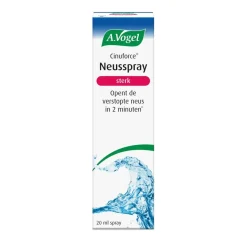

Gerelateerde producten

- Luchtwegen

- Neuszalf